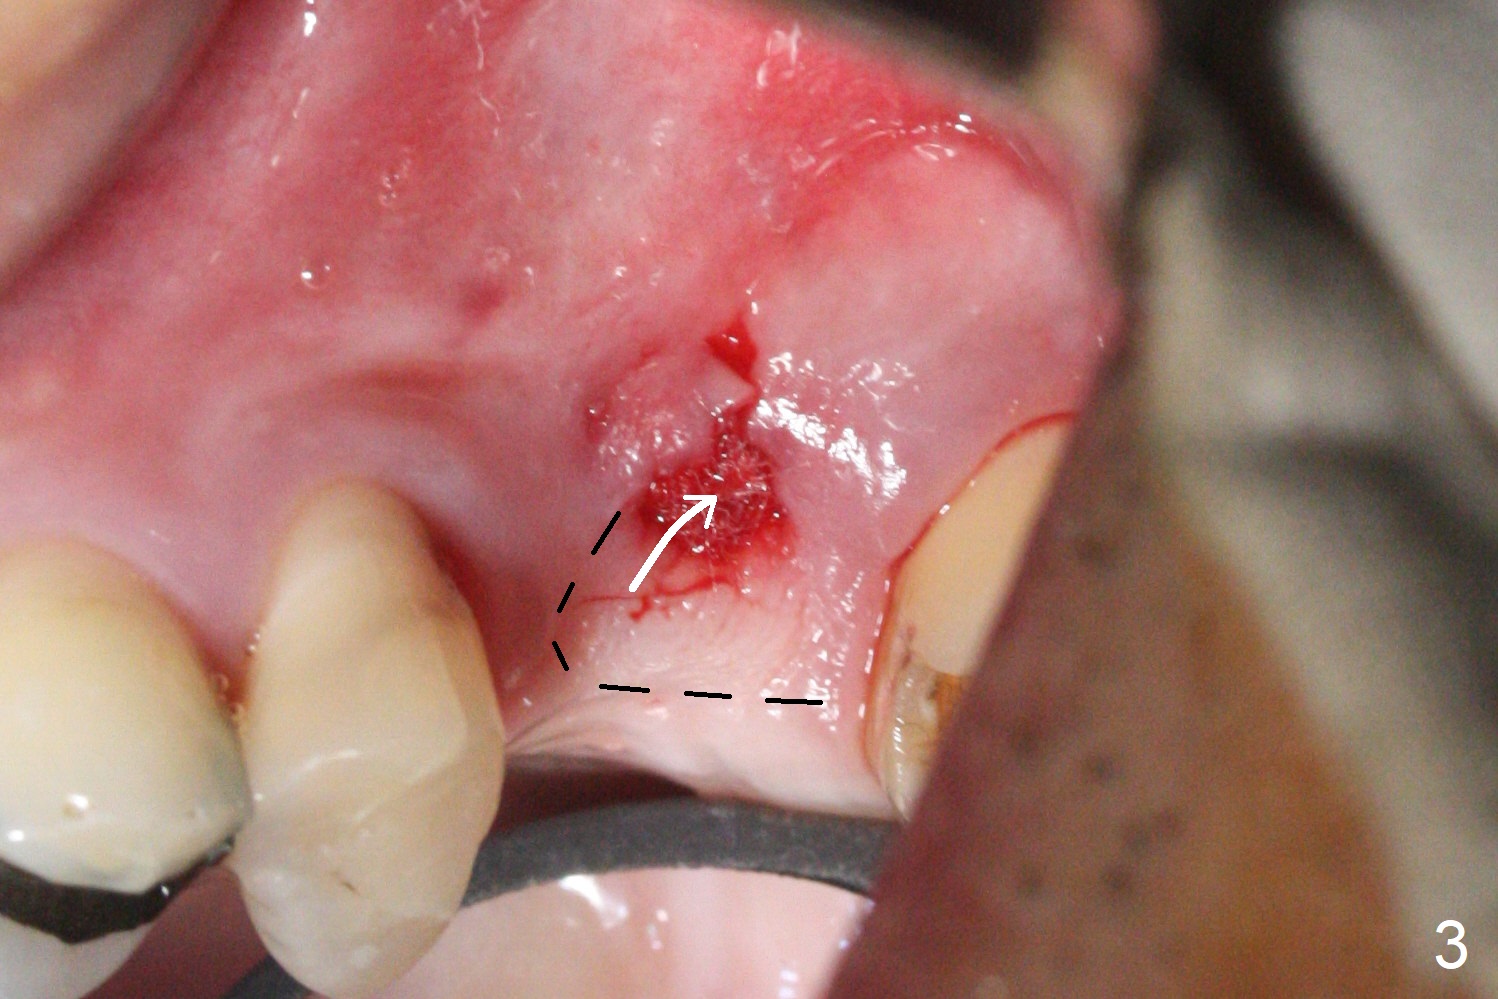

After extraction of the distobuccal residual root of the tooth #14 (Fig.1 arrow), the gingiva around the socket does not look like the keratinized one (Fig.2 *). An osteotomy through the distobuccal socket would seem too buccal for immediate implant. The palatal gingiva feels too tough to be stretched. An incision is made (Fig.3 dashed line); with elevation, the thick flap is transferred buccally (curved arrow). An osteotomy is initiated in the palatal bone with 1.5 mm drill, followed by Magic Expanders until 4.3 mm for 11 mm (Fig.4,5). Following Magic Drill 3.8x13 mm, the sinus membrane is found to be perforated. The latter is repaired with Osteogen plug. A 4.5x9 mm IBS implant is placed with 50 Ncm (Fig.6). Osteogen plug and allograft (Fig.7 *) are inserted into the remaining distobuccal socket (reduced after bone expansion). When a 5.5x4(4) mm abutment is placed, the transferred flap appears to be adapted to the distobuccal defect (Fig.8 *). Later one suture is placed for fixation. After provisional insertion, periodontal dressing is applied. Nine days postop, the periodontal dressing dislodges. When the loose provisional is removed for recementation, the flap seem to have healed (Fig.9 *). The gingiva heals around the abutment 5 months postop (Fig.9); the distal socket appears to heal while the bone graft remains at the crest (Fig.11,12). When #30 develops buccal abscess, the patient masticates on the left, leading to loss of composite at #13 (Fig.14); in fact the abutment at #14 is incompletely seated.